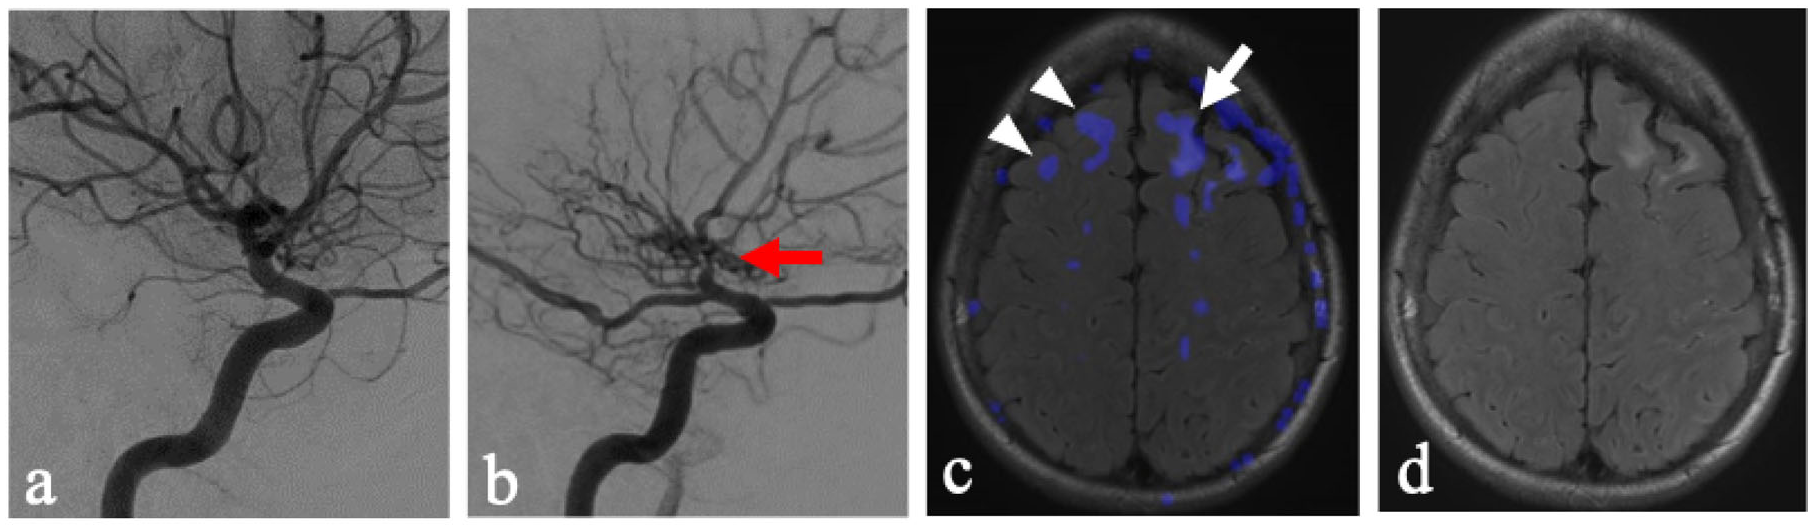

A few considerations must be observed in the current methodology. Patients with chronic unilateral steno-occlusive disease may have developed compensatory contralateral contributions from the NFLH to the FLH via the Circle of Willis. Additionally, the NFLH in these patients may also demonstrate decreased overall reserve due to exposure to the same vascular risk factors which lead to disease on the FLH. Lastly, acetazolamide as a stressor may be considered too extreme of a vasodilator when compared to states of physiologically increased demand. Quantitative generalizability is therefore limited in this evaluation as various factors may exaggerate steal phenomenon in our patient population. However, while these may exaggerate the degree of steal in NFLH, it nonetheless uncovers a key compensatory mechanism inherent to areas that have demonstrated a propensity for leukoaraiosis. Particularly illustrative cases of this phenomenon include pediatric patients without documentation of chronic hypertension and who were unlikely to have long-term sequalae or compensation of hypertensive pathology, who were found to display this pattern of steal after acetazolamide administration (Figure 3). This study lays the groundwork for comparison with healthy controls, which would provide more definitive analysis.

Figure 3. Two pediatric patients with unilateral vaso-occlusive disease of the right anterior circulation. (a) A right-sided ICA DSA with severe stenosis of the supraclinoid ICA (red arrow) corresponding to the FLH. (b) A left-side ICA DSA corresponding to the NFLH hemisphere. (c) Axial T2/FLAIR MRI with areas of steal phenomenon overlaid in blue, demonstrating the occurrence of steal within the NFLH (white arrowheads). The Fazekas for the right and left hemisphere were graded independently as 0 and 0. The steal for the right and left hemisphere were graded as 2 and 1, respectively. (d) A right-sided ICA DSA with severe stenosis of the supraclinoid ICA (red arrow) corresponding to the FLH. (e) A left-side ICA DSA corresponding to the NFLH hemisphere. (f) Axial T2 MRI with areas of steal phenomenon overlaid in blue, demonstrating the occurrence of steal within the NFLH (white arrowheads). The Fazekas for the right and left hemisphere were graded independently as 3 and 2, respectively. The steal for the right and left hemisphere were graded as 3 and 3, respectively.